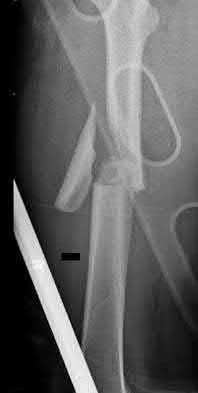

The image shows a reverse obliquity intertrochanteric hip fracture.

According to the referenced article by Haidukewych et al, unstable peritrochanteric hip fractures have a worse outcome (failed in 9/16 cases) if treated with a sliding hip screw. Two additional factors that were found to have a strong correlation with postoperative failure (nonunion, loss of reduction) were poor reduction and poor implant placement. In this study, fixed angle devices were superior. Intramedullary fixation has the added advantage of a shorter lever arm and less potential for fracture collapse and limb shortening.

The IMN also acts as a medial buttress.

According to Sanders et al, the dynamic condylar screw (DCS) can also be used in subtrochanteric models, but should not be used if extensive comminution is seen, as they reported a high failure rate with DCS in these fractures if highly comminuted. They report a 77% overall union rate with this device.